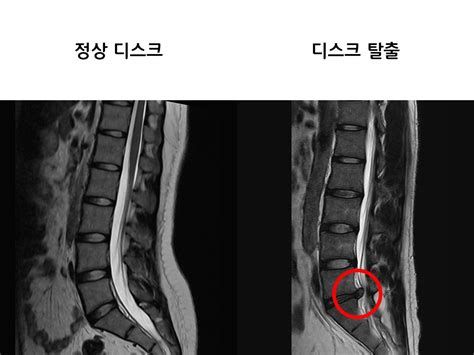

디스크(disc)는 척추뼈와 척추뼈 사이에 위치한 젤리 같은 물렁뼈 조직으로, 우리말로는 추간판이라고 부릅니다. 이 조직은 척추뼈끼리 직접 부딪히는 것을 막아주는 쿠션 역할을 하며, 척추의 움직임을 부드럽게 하고 외부 충격을 흡수하는 기능을 담당합니다.

디스크의 구조는 다음과 같습니다:

- 수핵: 중심부에 위치하며, 젤리처럼 말랑말랑하고 수분이 많아 충격을 흡수합니다.

- 섬유륜: 수핵을 둘러싸는 질긴 막으로, 수핵이 밖으로 빠져나가지 않도록 보호합니다.

디스크에 과도한 힘이 가해지거나 노화 등으로 인해 섬유륜이 손상되면, 내부의 수핵이 밖으로 튀어나올 수 있습니다. 이때 튀어나온 수핵이 신경을 압박하여 통증이나 감각 이상, 심하면 마비 증상까지 유발할 수 있는데, 이를 흔히 **허리디스크(요추 추간판 탈출증)**라고 부릅니다.